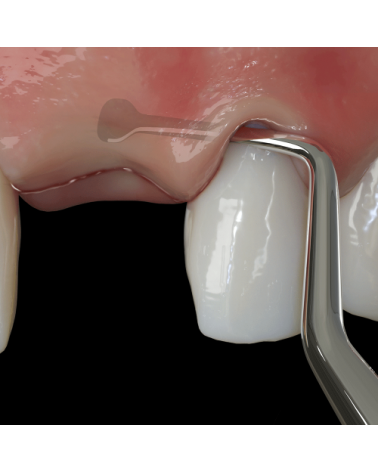

Пародонтальний ніж Nanos A застосовується для супраперіостального розсічення апікально та латерально під час тунелювання та хірургічних втручань на м'яких тканинах. Цей інструменти також корисний у створенні часткового або повного товстого клаптя конверта під час процедур трансплантації сполучної тканини в періопластичній хірургії та імплантації. Пародонтальний ніж Nanos A також дуже ефективний при піднятті клаптя в лінгвальній зоні і зоні піднебіння під час хірургічної операції.